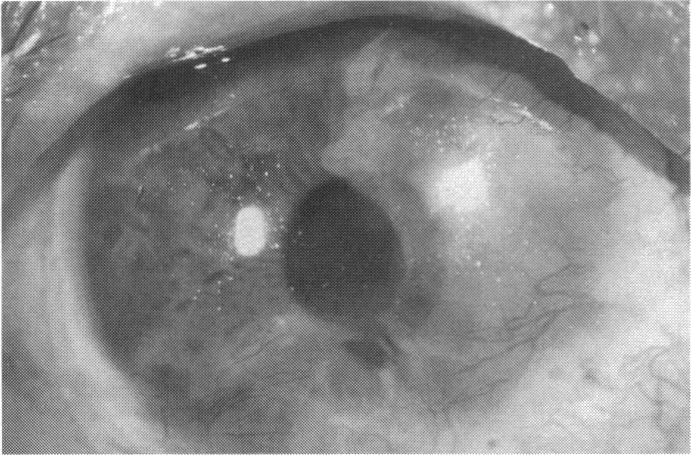

RESULTS

Human subjects. Of the 19 total patients admitted to the study, the presumed corneal epithelial stem cells of 1 patient did not grow in vitro. Of the remaining 18 patients (20 procedures, 19 eyes), 3 patients had unsuccessful results (3 autologous procedures), 1 patient had a partially successful procedure (allogeneic procedure), and 1 patient had a procedure with an undetermined result at present (allogeneic procedure). One unsuccessful patient had entropion/trichiasis and mechanically removed the graft and eventually went into phthisis. The other 2 unsuccessful patients suffered presumed loss of autologous donor epithelium and recurrence of the ocular surface disease (pterygium). The partially successful patient receiving an allogeneic transplant had infectious keratitis delay of his re-epithelialization; he has only minimal visual improvement but has re-epithelialized. The patient receiving the second allogeneic graft lost his donor epithelium at day 4. Additional donor epithelium was reapplied, but the result is undetermined at present. Amniotic membrane as carrier. The in vitro preparation of the amniotic membrane with corneal epithelial stem cell graft overlay was successful. Histology documented removal of the amniotic epithelium and reapplication of corneal epithelial cells. Animal model. The 2 rabbits that had no reparative surgery following standard ocular surface injury had histology and immunopathology consistent with incomplete corneal epithelial stem cell failure with vascularization and scarring of the ocular surface. Light microscopy and immunohistologic staining with AE5 confirmed the conjunctival phenotype of the ocular surface repair but also documented the incomplete model. The allogeneic stern cell transplants had varying results. One rabbit had a suppurative infection and lost the graft. Reparative surgery failed in 2 of the rabbits, failed partially in 3 of the rabbits, was partially successful in 3 others, and was successful in 1 rabbit at 28 days. Histologic and immunopathologic study documented successful growth of corneal epithelium onto the recipient surface.

结果

人类受试者。纳入研究的19例患者中,1例患者的假定角膜上皮干细胞在体外未生长。其余18例患者(20例手术,19只眼)中,3例患者手术结果不佳(3例自体手术),1例患者手术部分成功(异体手术),1例患者目前手术结果未确定(异体手术)。1例手术失败的患者患有睑内翻/倒睫,机械性移除了移植物,最终眼球萎缩。另外2例手术失败的患者假定自体供体上皮丢失且眼表疾病(翼状胬肉)复发。接受异体移植的部分成功患者发生感染性角膜炎,上皮化延迟;他的视力仅略有改善,但已重新上皮化。接受第二次异体移植的患者在第4天失去了供体上皮。重新应用了额外的供体上皮,但目前结果未确定。羊膜作为载体。羊膜与角膜上皮干细胞移植物覆盖物的体外制备成功。组织学证实羊膜上皮已去除且角膜上皮细胞已重新应用。动物模型。2只在标准眼表损伤后未进行修复手术的兔子的组织学和免疫病理学结果与角膜上皮干细胞不完全衰竭一致,伴有眼表血管化和瘢痕形成。光学显微镜检查和用AE5进行的免疫组织化学染色证实了眼表修复的结膜表型,但也记录了不完全模型。异体干细胞移植结果各异。1只兔子发生化脓性感染,移植物丢失。2只兔子的修复手术失败,3只兔子部分失败,另外3只部分成功,1只兔子在28天时成功。组织学和免疫病理学研究记录了角膜上皮在受体表面的成功生长。